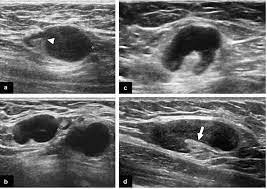

Figure 2 From Sonographic Features Of Inflammatory Breast Cancer Semantic Scholar

Figure 2 From Sonographic Features Of Inflammatory Breast Cancer Semantic Scholar from d3i71xaburhd42.cloudfront.net

It's called inflammatory because that's how it looks. Any area that does not look like normal tissue is a possible cause for concern. Inflammatory breast cancer, also known as carcinomatous mastitis, t4d, or pev 2 or 3, is the only real therapeutic emergency in breast oncology, given the high risk of metastasis, the reason for the most unfavourable prognosis of all breast cancers.it must consequently be diagnosed rapidly, and imaging examinations must in no case delay therapeutic management. Because ibc grows quickly, it is usually found at a locally advanced stage, meaning that cancer cells have spread into nearby breast tissue or lymph nodes. A breast ultrasound is a scan that uses penetrating sound waves that do not affect or damage the tissue and cannot be heard by humans. Ultrasound is useful for looking at some breast changes, such as lumps (especially those that can be felt but not seen on a mammogram) or changes in women with dense breast tissue. As these inflammatory breast cancer picture shows, the texture of the breast may change and appear to look dimpled or ridged, like an orange peel. Their differences, however, lie in their enhancement.

Most inflammatory breast cancers are invasive ductal carcinomas, which means.

However, inflammatory breast cancers are more likely to show solid mass lesions. The problem is that inflammatory breast cancer can look very much like mastitis early on, and is often diagnosed only after a woman has been treated first for mastitis (often with no improvement in symptoms). This condition usually does not develop a lump, but commonly affects the breast skin. The aim of this study was to evaluate the features of inflammatory breast carcinoma (ibc) on mri compared with mammography and ultrasound and to better define the role of mri in patients with this aggressive disease. These tubes, which are hollow, allow lymph fluid to drain out of the breast.